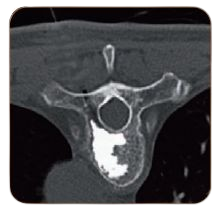

CementoFixx ist ein viskoser Zement für die Vertebroplastie und Kyphoplastie. Er besitzt eine hohe Viskosität und ein großzügiges Arbeitszeitfenster. Außerdem hat er gute mechanische Eigenschaften und ein gutes Mischverhältnis. Der Zement ist exzellent röntgensichtbar und somit während der gesamten Prozedur gut zu kontrollieren. Komplikationen durch unerwünschte Zementleckagen können somit vermieden werden. |